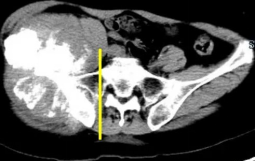

术前截骨规划

据主刀医师徐生林介绍,本例病例将整个右侧半骨盆Ⅰ+Ⅱ+Ⅲ+Ⅳ区(累及骶骨)进行整块切除,同时切除肿瘤覆盖的部分骶骨。3D打印假体所有骨接触界面均设计为骨整合结构,有利于骨长入和骨盆假体的永久稳定。耻、坐骨结构不规则,因此设计组配式结构,有利于术中操作,极大地方便了术中的假体安装。